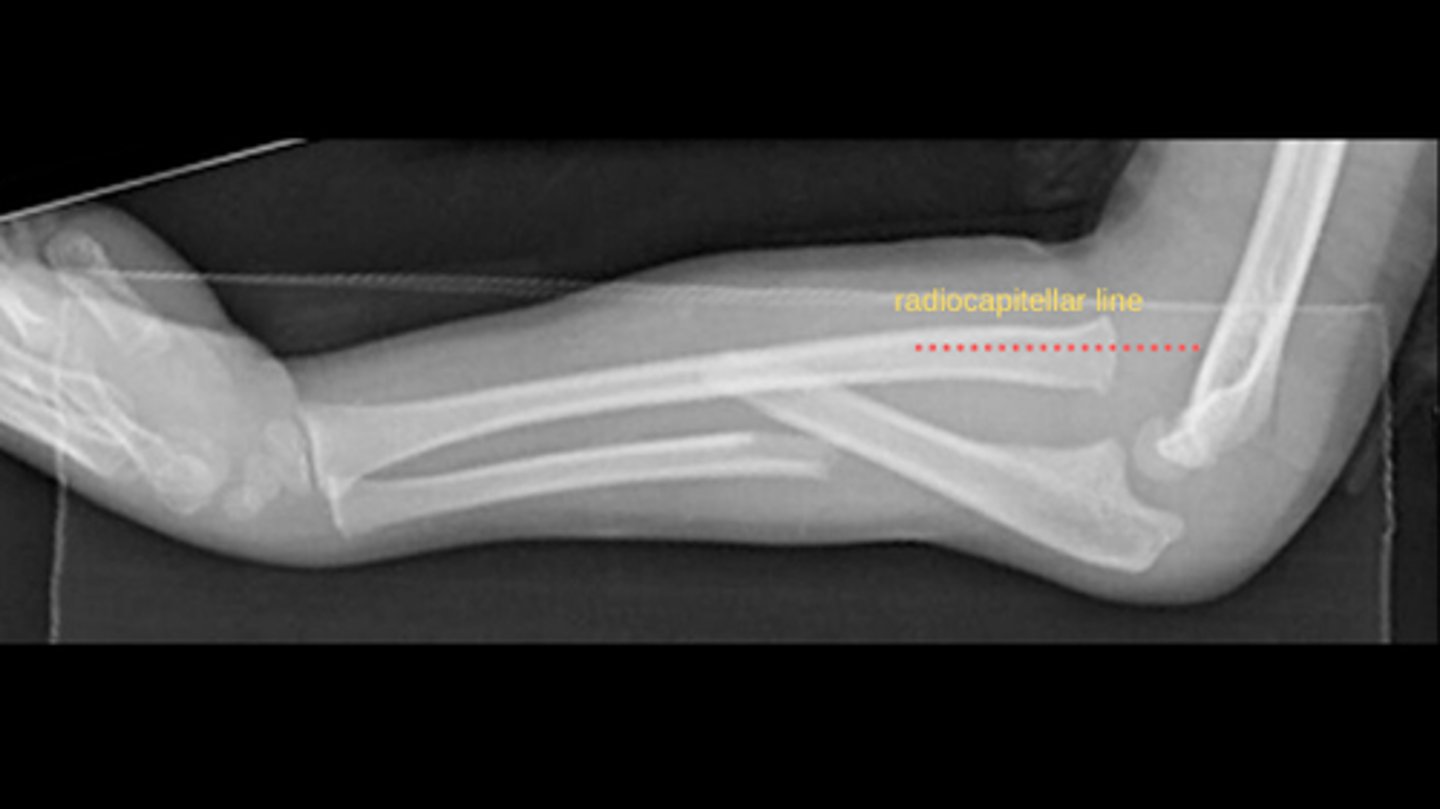

What is a "Monteggia fracture"?

Ulnar fracture --> dislocation of radio-humeral joint